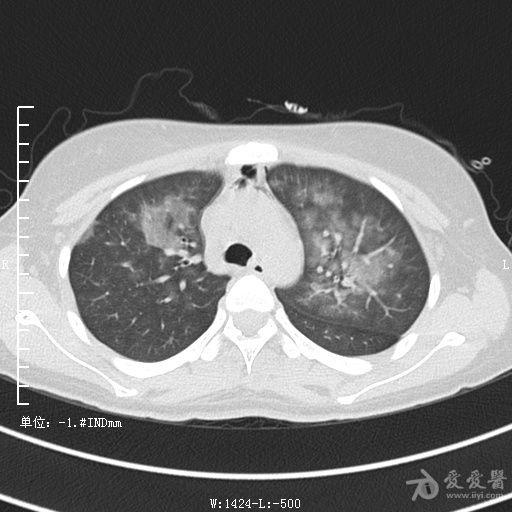

典型支气管扩张及肺水肿CT片

典型支气管扩张肺水肿